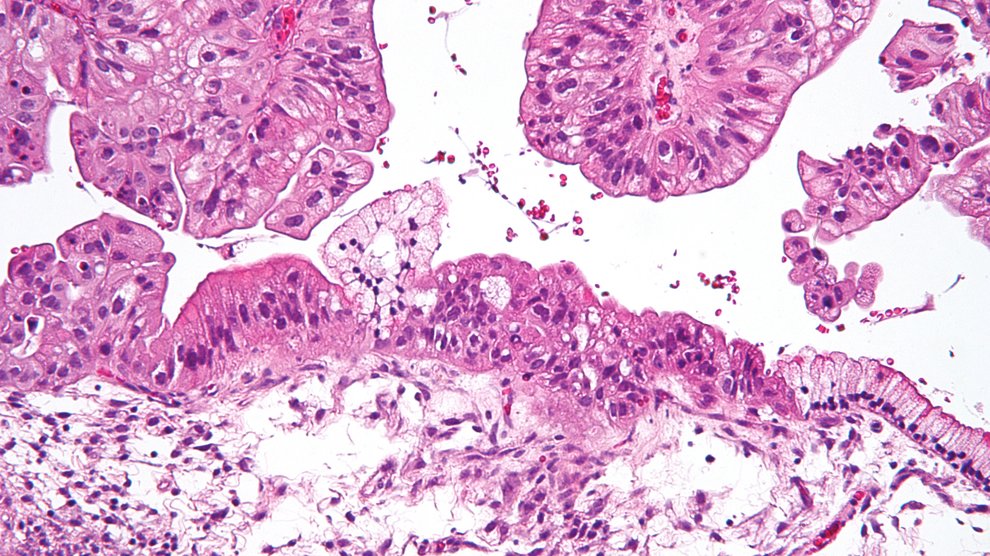

Would you remove an organ to reduce cancer risk based on the results of a genetic test? Women predisposed to ovarian cancer are facing that difficult decision. Freelance journalist Charlotte Huff reports the story, originally published in Mosaic .